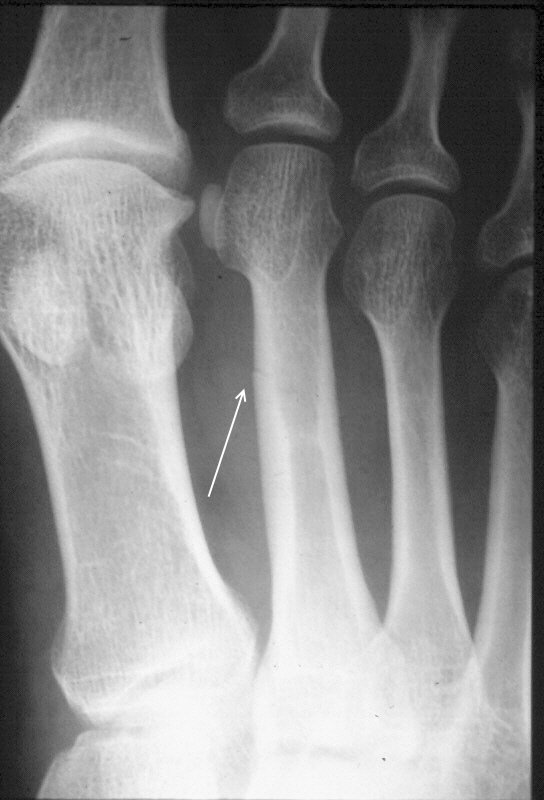

Stress fractures are notoriously difficult to diagnose. Superficially, there is typically swelling, pain, and redness. In the early stages on x-ray, a very faint line is present, this faint line can be confused with blood vessel marks in the bone or just overlooked all together. At 2 weeks the bone starts to display signs of bone heeling, this is evident by fluffy bone growth around the fracture site- called callus formation. When the callus formation is visible a stress fracture is much easier to diagnose. If it is uncertain if there is a stress fracture, an MRI, CT, or bone scan can be done, these radiology studies make it very ease to identify any abnormalities in the bone.

- Notice the faint line where the stress fracture is present